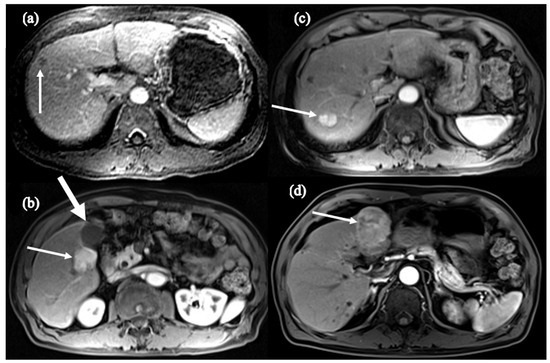

- Shinn, B.J.; Martin, A.; Coben, R.M.; Conn, M.I.; Prieto, J.; Kroop, H.; DiMarino, A.J.; Hann, H.W. Persistent risk for new, subsequent new and recurrent hepatocellular carcinoma despite successful anti-hepatitis B virus therapy and tumor ablation: The need for hepatitis B virus cure. World J. Hepatol. 2019, 11, 65–73. [Google Scholar] [CrossRef] [PubMed]

- Boortalary, T.; Shinn, B.; Coben, R.M.; Conn, M.I.; Prieto, J.; Kroop, H.; Dimarino, A.; Hann, H. Are We Close to Achieving a HBV Cure? Risk for Hepatocellular Carcinoma Persists Despite Long-term HBV Suppression: An Update on Our Experience. Arch. Gastroenterol. Res. 2020, 1, 105–110. [Google Scholar]

- Chowdhury, S.; Garrido, D.; Halegoua-DeMarzio, D.; Roth, C.; Hann, H.W. Poor Prognosis in HBV-associated Hepatocellular Carcinoma After Successful Viral Suppression: A Case Series Highlighting a Need for a Cure. J. Immunol. Sci. 2023, 7, 1–8. [Google Scholar] [CrossRef]